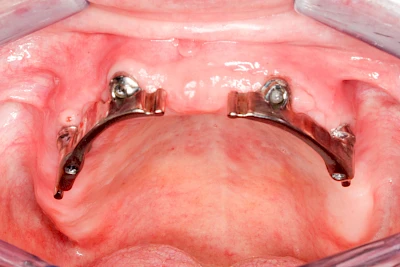

Implantate: Prothesen

Bei herausnehmbaren Prothesen werden Implantate eingesetzt, um den Halt und den Tragekomfort der Prothesen zu verbessern. Dazu kommen verschiedene Verbindungselemente zum Einsatz:

- Teleskope

- Kugelköpfe

- Tellerförmige Lokatoren

- Stege

- Magnete (selten)

Neben rein implantat-getragenen zahnärztlichen Versorgungen werden bei herausnehmbaren Prothesen Implantate auch in Sinne einer "strategischen Pfeilervermehrung" ergänzend zu eigenen Zähnen zur Verankerung eines Zahnersatzes genutzt.

Varianten zur Verankerung von abnehmbarem Zahnersatz auf Implantaten